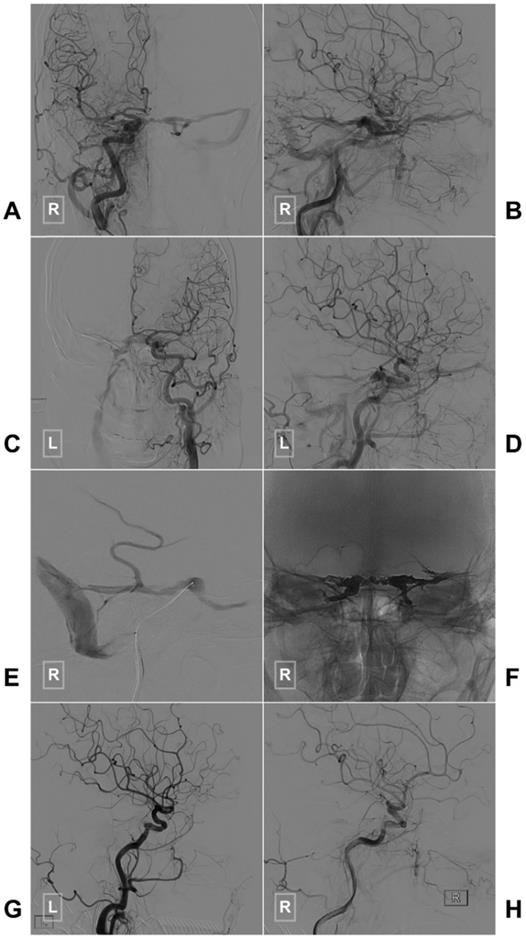

Figure 2

Typical case of a CS-DAVF with TVE via the IPS. An angiogram of the right (A-B) and left (C-D) common carotid arteries in AP (A, C) and lateral (B, D) views shows a CS-DAVF supplied by the bilateral dural branches of ECA and ICA. E, The microcatheter advances to the CS via the right IPS. F, The bilateral CSs are packed by Onyx. G-H, A postprocedural angiogram of the right common carotid artery in the lateral view shows that the CS-DAVF is obliterated. Abbreviations: AP, anteroposterior; CS, cavernous sinus; CS-DAVF, cavernous sinus dural arteriovenous fistula; ECA, external carotid artery; ICA, internal carotid artery; IPS, inferior petrous sinus; L: left; R: right; TVE, transvenous embolization.

If the SP packing is not satisfactory or the CS-DAVF belongs to the proliferative type according to Suh et al.'s classification, the entire CS has to be packed densely [38]. A case of CS-DAVF with entire CS packing via IPS is illustrated in Figure 2.